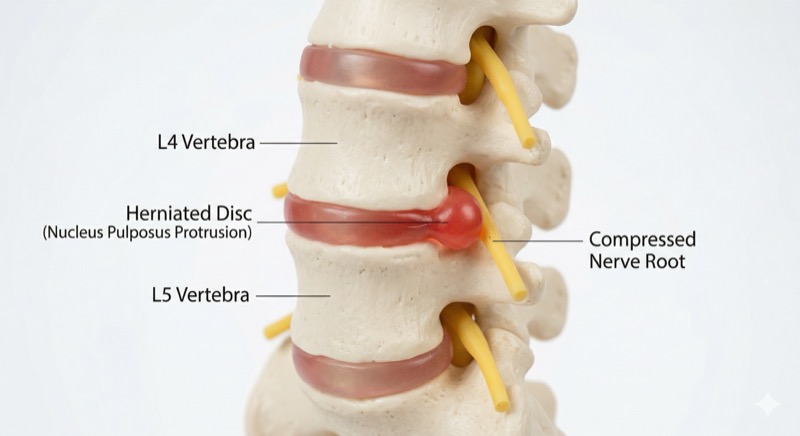

¿Traumatólogo o neurocirujano? Cuando el problema es la columna, la pregunta correcta es otra: que su especialista se dedique de verdad a la columna. Le explico la diferencia, qué preguntar en la consulta y por qué la mayoría de los dolores de espalda no se opera.